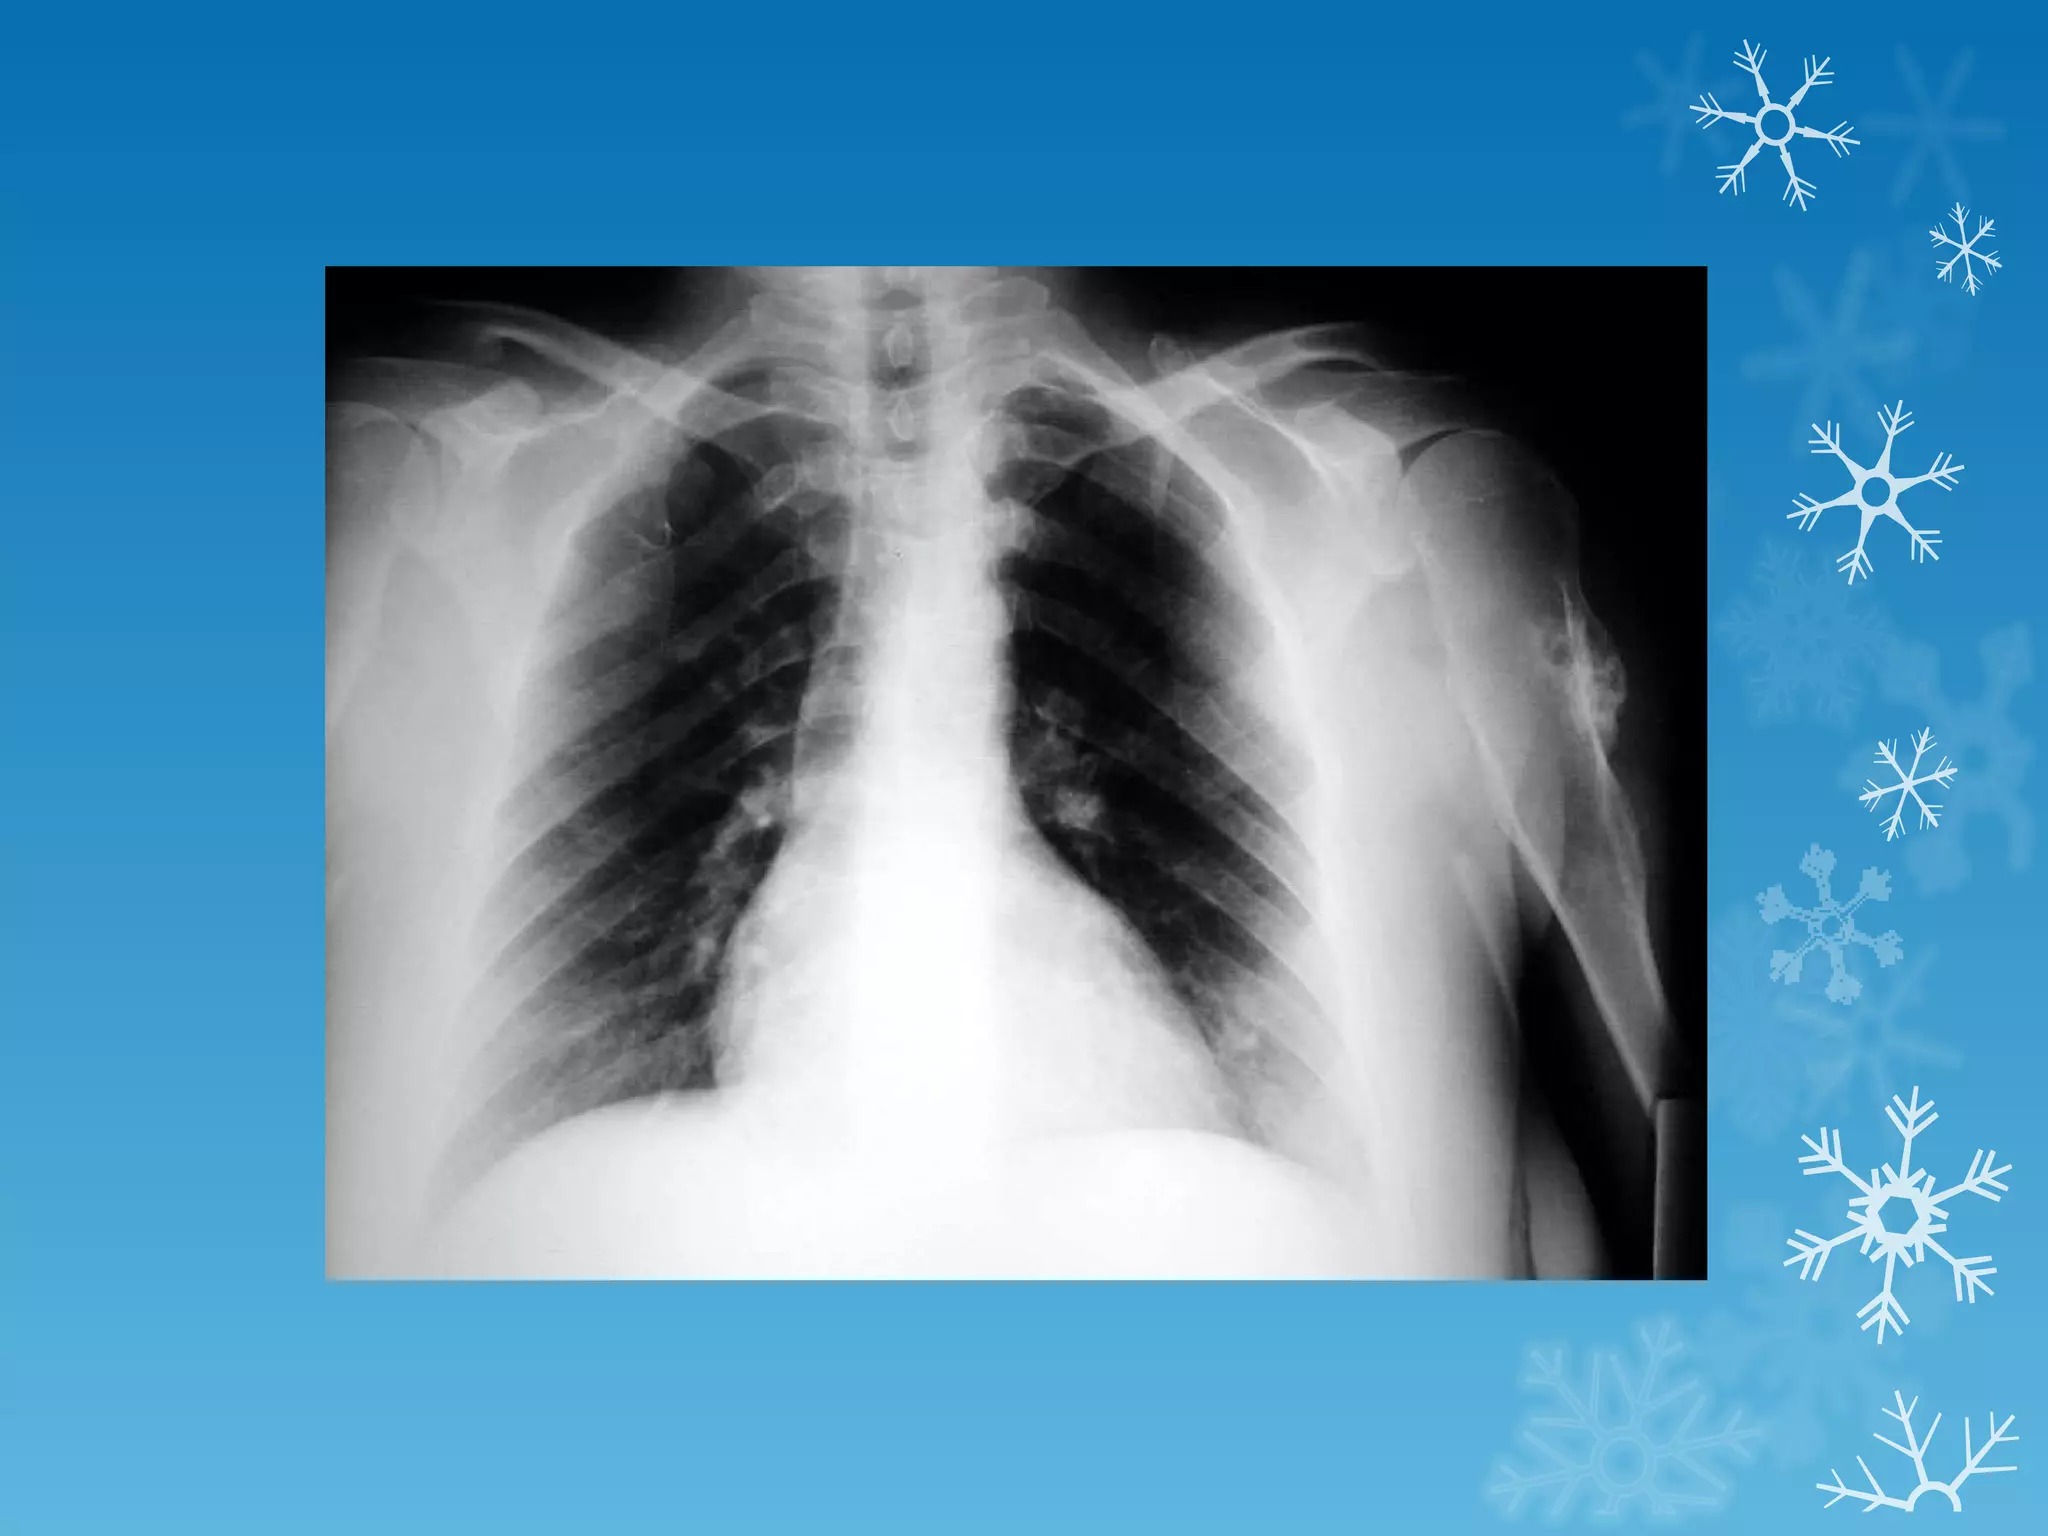

This document discusses chest x-ray interpretation and provides guidance on evaluating x-rays. It explains that tissue density determines how an x-ray beam penetrates, with denser tissues appearing whiter and less dense tissues appearing blacker. It also outlines different chest x-ray views and factors to consider like patient orientation, age, gender, and rotation. Abnormalities are described as appearing too white, too black, too large, or in the wrong place. The document stresses a systematic approach of identifying, localizing, describing lesions, and providing differential diagnoses.